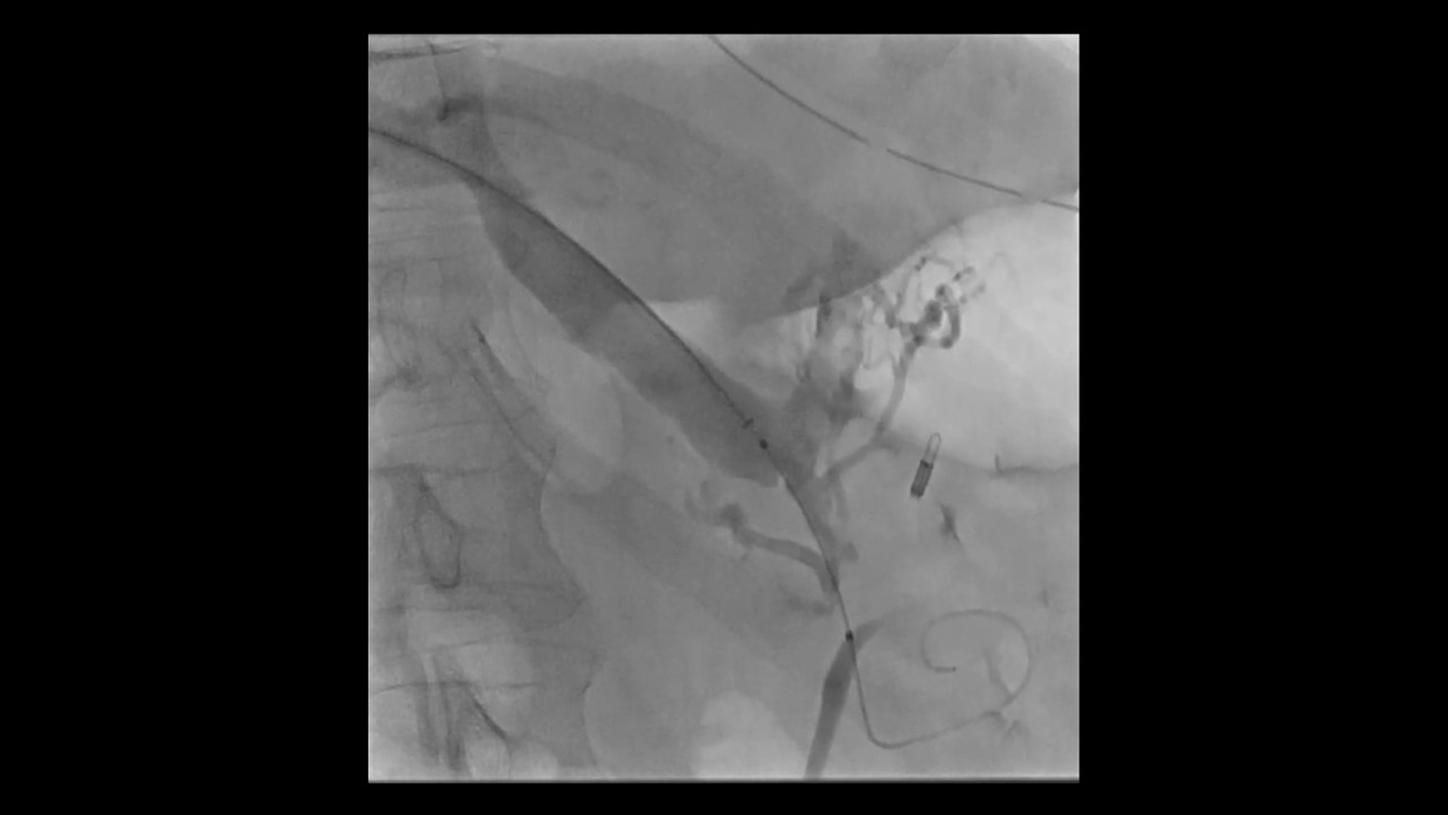

During minimally invasive procedures, it is critical to have a clear view of anatomies and devices. Yet complex imaging tasks or challenging patient conditions often impact image quality. OPTIQ AI delivers constant image quality1 defined by CNR in support of the ALARA principle, independent of patient or C-arm angulation. On top, an AI-powered algorithm reduces image noise in real time across different 2D imaging modes.

Make AI-powered imaging and clear insights your standard during interventions – with OPTIQ AI.

Future-focused IR imaging for a broad procedure mix

Discover how leading clinicians are transforming interventional radiology with Siemens Healthineers technologies. From ultra-fast 3D imaging to laser-guided needle procedures, the ARTIS icono ceiling powered by OPTIQ and syngo DynaCT are redefining what’s possible in IR. Explore real-world cases, expert insights, and the future of image-guided therapy.